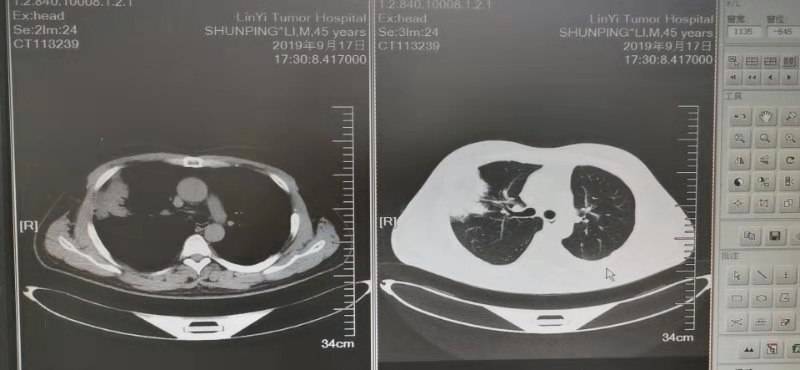

战战兢兢走过三年多点,这次复查有变化,化疗实在是不想再用了,老公身体状况很好和正常人一样,只是身体里有个不老实的总是反反复复折磨着人。16年5月份左肺下页手术,一年后复发,基因检测两次都是阴性,易瑞沙也盲试过无效 ,只能一直化疗,身体不耐受了就赶快停下来养精蓄锐,本来期待能老老实实的安稳两三年,哪想到复查七月份复查又有变化,盲吃了克唑替尼一个月也是无效。8月份右肺穿刺重新做检测,这次我们是幸运儿,有新突变但是不知道先用哪种好?